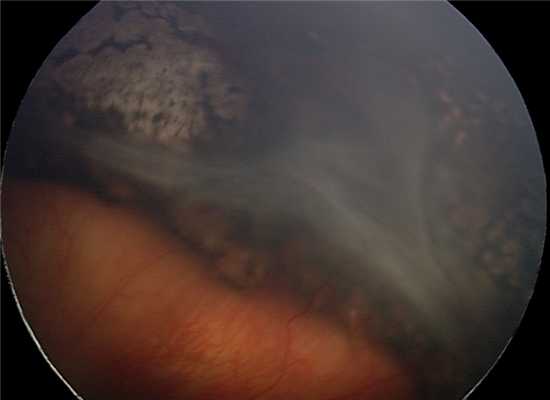

Клинический случай.

Глазное дно ребёнка А. до операции.